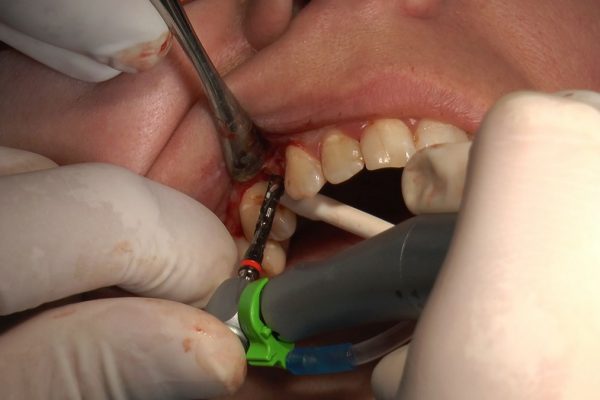

W ostatni weekend czerwca 2018 roku kursanci II Sezonu Preludium Implantologii odbyli piątą, finałową sesję, która w całości podporządkowana była praktyce. W ciągu dwóch dni zabiegowych Lekarze uczestniczący w szkoleniu przeprowadzili szereg zabiegów pod kierunkiem dr n.med. Violetty Szycik. Wszczepili 17 implantów oraz przeprowadzili ekstrakcje i zabiegi regeneracyjne kości. Zabiegi były wykonywane także w sedacji dożylnej z udziałem specjalisty anestezjologii i intensywnej terapii dr Jolanty Grzybowskiej. Preludium implantologii to nowy program edukacyjny dla adeptów implantologii stomatologicznej, którego celem jest wprowadzenie do implantologii poprzez pozyskanie wiedzy w szerokim zakresie i uwzględnieniem szczegółów mających decydujące znaczenie dla powodzenia leczenia implantologicznego. Ale tak jak wszystkie szkolenia w Instytucie Vivadental, w tym wiodące Practiculum Implantologii, zorientowane jest na praktyce i samodzielnym wykonywaniu zabiegów pod kierunkiem Mentora. To najlepsza edukacja w medycynie zabiegowej, a zarazem najlepszy start do implantologii.